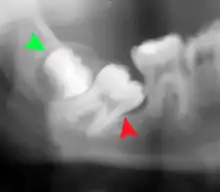

يمكن أن تشمل المضاعفات طويلة الأجل مضاعفات اللثة مثل فقدان العظام على الضرس الثاني بعد إزالة ضرس العقل. يعد فقدان العظام من المضاعفات بعد إزالة الأسنان الحكيمة أمرًا غير مألوف لدى الشباب ولكنه يتواجد في 43٪ من الأشخاص البالغين من العمر 25 عامًا أو أكبر. الإصابات في العصب السنخي السفلي الذي يؤدي إلى تنميل أو خدر جزئي في الشفة السفلية والذقن يحدث بمعدلات تتفاوت بشكل كبير من 0.04٪ إلى 5٪. أكبر دراسة مأخوذة من دراسة استقصائية أجريت على 535 من جراحي الفم والوجه والفكين في كاليفورنيا، حيث تم الإبلاغ عن معدل 1: 2500.[23]

استئصال التاج هو إجراء يتم فيه إزالة تاج ضرس العقل المنطمر، ولكن يتم ترك الجذور في مكانها عن قصد. يشار إلى أنه يمكن عمله عندما لا يكون هناك مرض في لب الضرس أو عدوى حول تاج الضرس، وهناك خطر كبير من إصابة العصب السنخي السفلي .[28]

في حين أن استئصال التاج يقلل الخطر المباشر على وظيفة العصب السنخي السفلي فإن لديه معدلات مضاعفاته الخاصة ويمكن أن يؤدي إلى عمليات جراحية متكررة. يتم تخلخل ما بين 2.3٪ و 38.3٪ من الجذور أثناء العملية وتحتاج إلى إزالتها وتحتاج نسبة 4.9٪ من الحالات إلى إعادة العملية بسبب الألم المستمر أو تعري الجذر أو الالتهابات المستمرة. كما تم الإبلاغ عن تحرك الجذور وتغير مكانها في 13.2 ٪ إلى 85.9 ٪ من الحالات.[28]